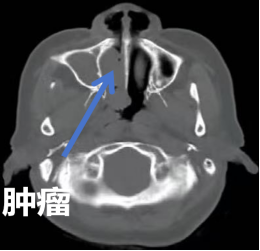

据了解,王女士患过敏性鼻炎多年,有时还会鼻出血,症状重时需要药物治疗,基本可控制缓解鼻部不适。最近20天以来,鼻部症状逐渐加重,药物治疗效果差,伴有莫名奇妙的异味,并出现鼻涕中带血丝,嗅觉明显减退,有时还会出现鼻出血等症状。当地医院CT检查报告为:鼻腔鼻窦病变。王女士立即到哈医大二院耳鼻咽喉头颈外科就诊,通过进一步的鼻内镜检查,医生发现了黑色肿物,经过病理活检证实为鼻腔恶性黑色素瘤。

完善各项术前检查后,孙亚男教授团队经病例讨论后确定周密的外科手术治疗方案,在鼻内镜的精准视野下,充分暴露术区,明确肿瘤安全界限,扩大切除肿瘤。在医护人员精心守护下,手术效果立竿见影。术后第二天,取出鼻腔止血材料后,王女士鼻腔通气功能完全恢复,折磨了王女士20余天的鼻出血症状也基本消失,同时精神状态也明显好转,待身体进一步康复后进行后续的综合治疗。